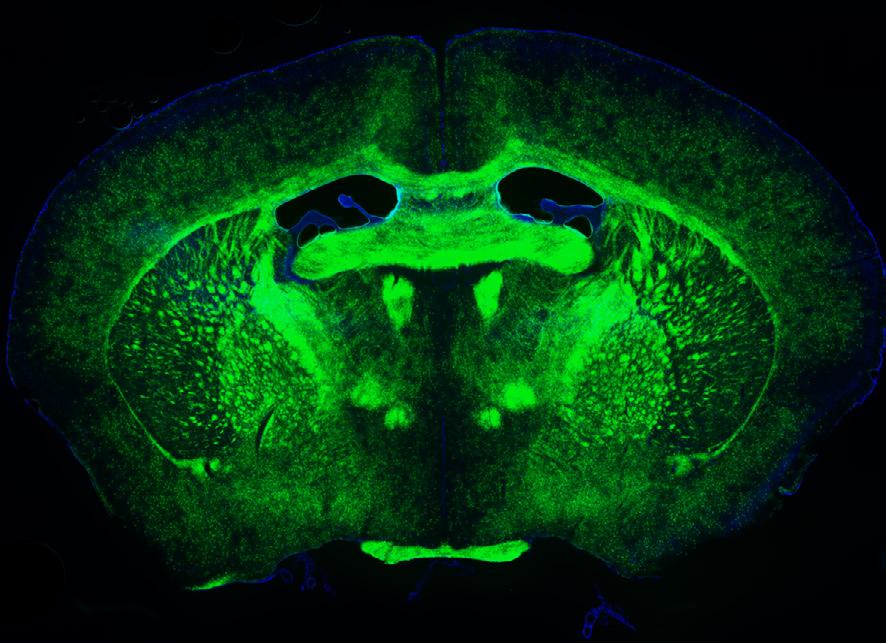

Established in 2023 under the leadership of Luke Hammond, the Quantitative Imaging Platform is transforming neurological research at Ohio State. This cutting-edge resource provides access to advanced microscopes, computational tools, and deep learning techniques, enabling breakthroughs in understanding neurological diseases that were previously out of reach.

The platform features state-of-the-art equipment, including a spinning disk confocal microscope for live imaging, super-resolution imaging, and high-throughput analysis of cells and tissues. These unique tools empower researchers to tackle complex questions with precision and efficiency.

Currently, the platform supports a wide range of projects, from studying how axons regenerate and how neurons interact with the immune system to analyzing microglial shapes and conducting whole-brain imaging. These collaborations are creating reliable workflows that fuel innovative discoveries, strengthen grant proposals, and lead to impactful scientific publications.

Looking ahead, the platform aims to expand its capabilities even further. Plans include enabling researchers to image entire brains and spinal cords using advanced light sheet microscopy, observe cellular activity in real time with in vivo imaging, and analyze human nervous tissue.

Astrocytic endfeet and arborization over a brain capillary and surrounding microenvironment. (Subhodip Adhicary, PhD)